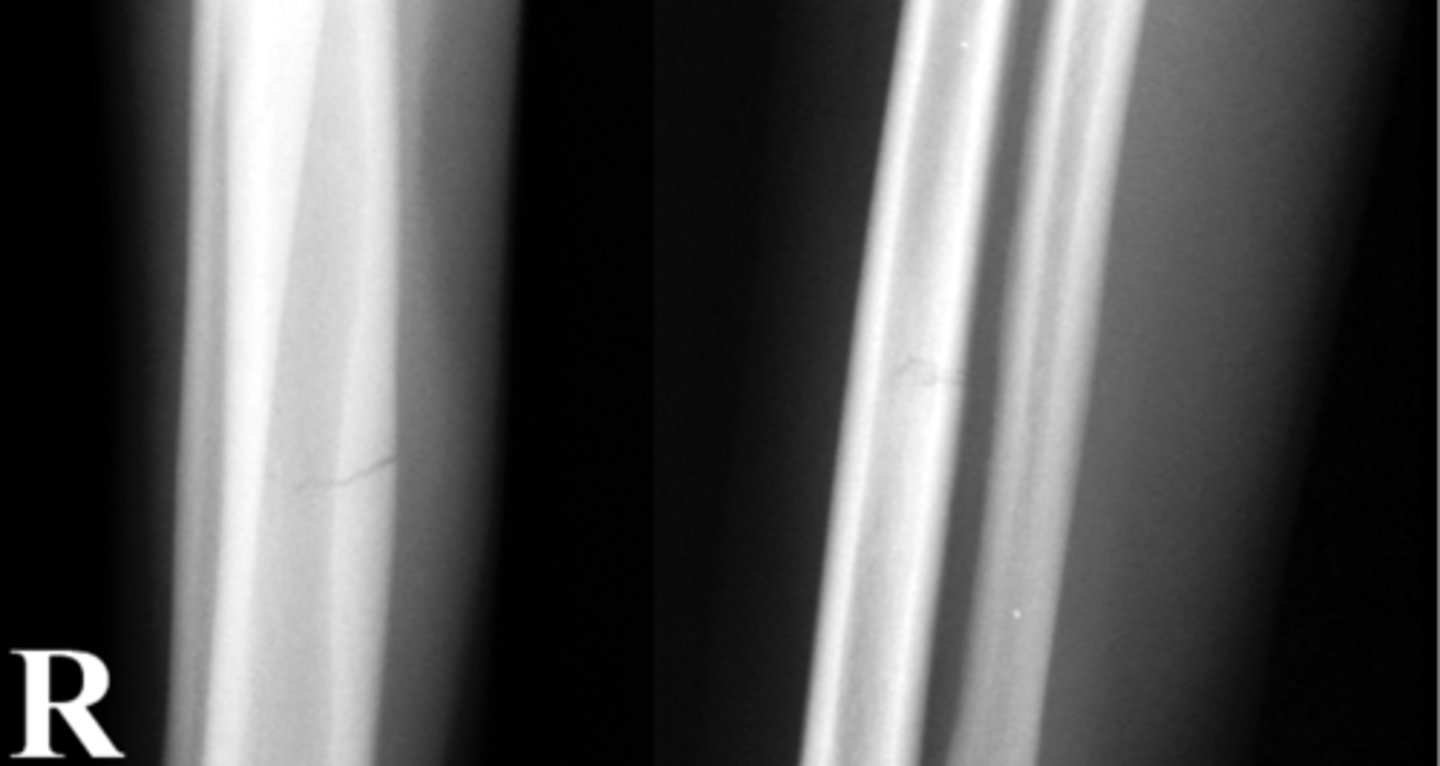

Identify the fracture type?

Incomplete fracture

What kind of stress will cause a incomplete fracture?

Repetitive stress remodling